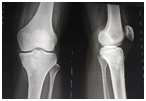

Her leg radiograph revealed sclerosis in the metaphysis of the proximal tibia, (Figure 1).

Figure 1 Radiograph of the left knee. There is a sclerotic lesion in the proximal tibia.